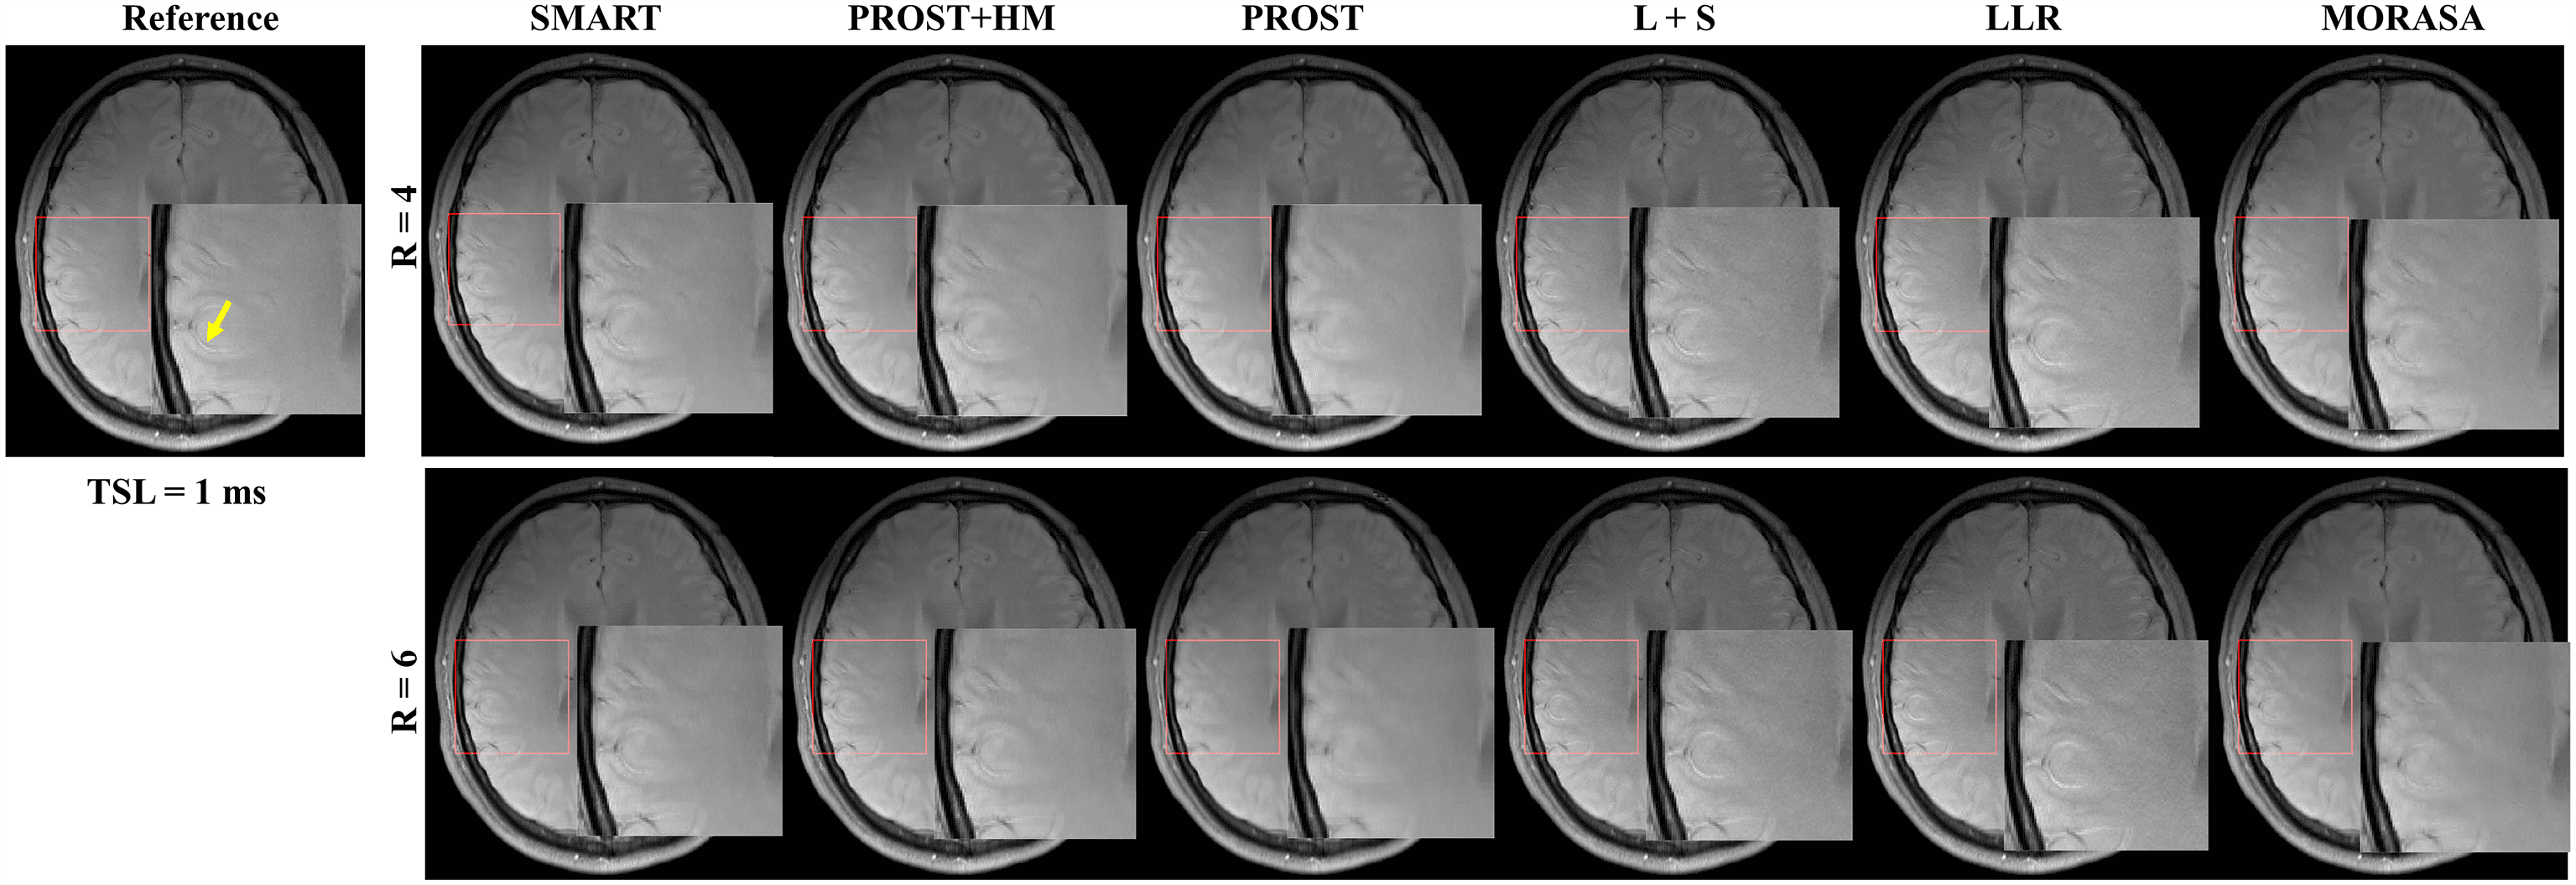

The -weighted images (at TSL = 1 ms) from one volunteer reconstructed using the SMART, PROST+HM, PROST, L+S, LLR, and MORASA methods are shown in Fig. 3. Difference images between the reconstructed and reference images are displayed under the reconstructions, and the nRMSE values are placed below the difference images. Table 1 lists the average HFEN, SSIM, and PSNR values for all reconstructed -weighted images at different TSLs. The estimated maps from the reconstructed and difference images are shown in Fig. 4.

Supplementary information Fig. S2 shows the reconstructed -weighted images (at TSL = 1 ms) and the magnified images of the ROI from another volunteer using the SMART, RROST + HM, PROST, L + S, LLR, and MORASA methods at R = 4 and 6, respectively. The SMART method can better preserve the image resolution and finer details than the RROST + HM, PROST, and MORASA methods. The L + S and LLR methods have an image enhancement effect in the reconstructed images, particularly in the sulcus area, which is indicated by the yellow arrow. Compared to the methods exploiting spatial low-rankness (PROST, L + S, and LLR methods), the reconstruction can be improved by using parametric low-rankness based on high correlations in signal evolution in the reconstruction model.

Fig. 6 shows the prospective reconstructed -weighted images (at TSL = 40 ms) from another volunteer and the magnified images using the SMART, PROST + HM, PROST, L + S, LLR, and MORASA methods. Visual artifacts can be observed in the magnified images of reconstructions at all accelerating factors using the L + S and LLR methods. The images reconstructed using the PROST + HM and PROST methods were blurred compared to those reconstructed using the SMART method. Some image details (namely, the blood vessel marked in a yellow arrow) can narrowly be seen in the reconstructions using the PROST + HM and MORASA methods and disappeared in the reconstruction using the PROST method at R = 5.76. In contrast, the image details were well preserved using the SMART method. The maps reconstructed using the methods above are shown in supplementary information Fig. S4. Similar conclusions can be drawn from the maps.